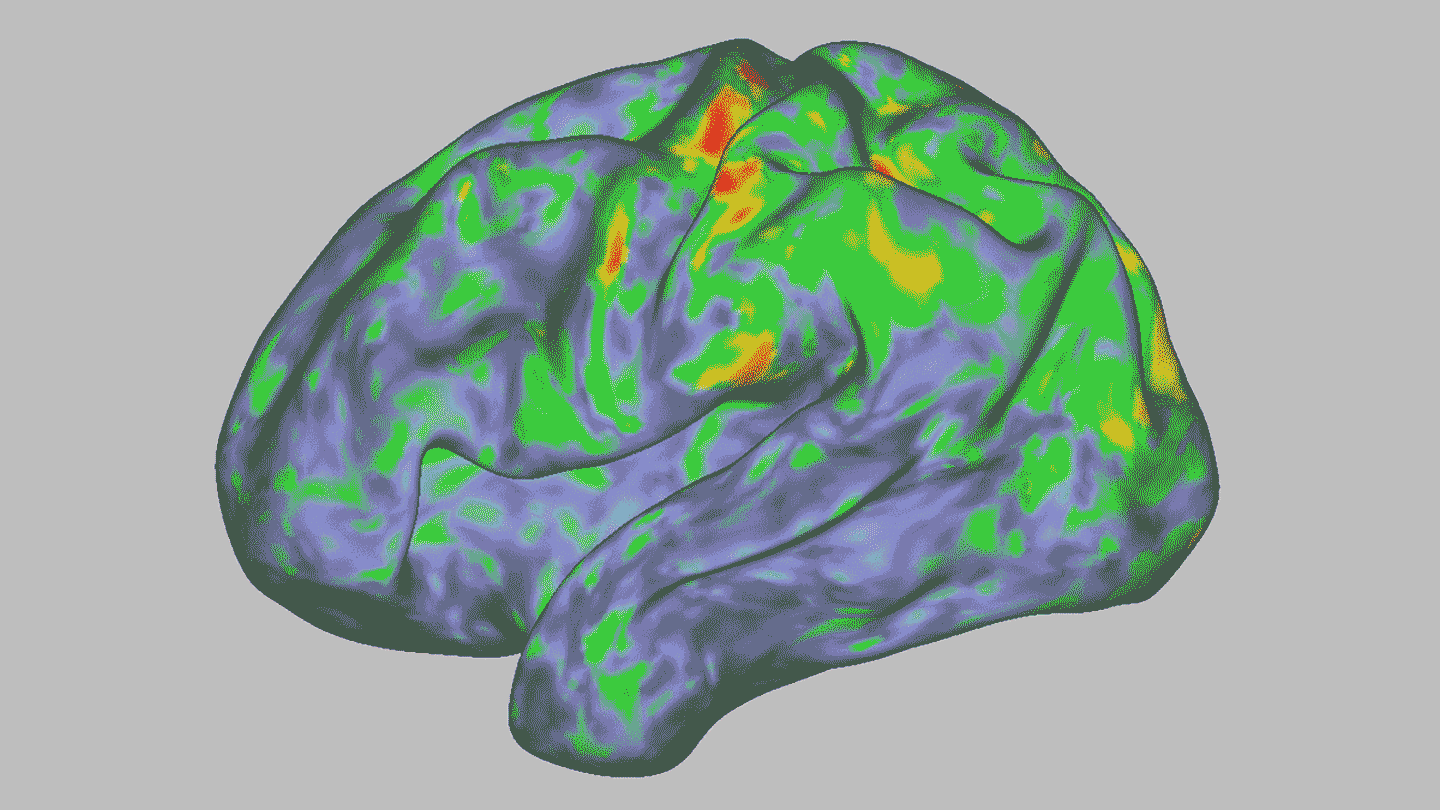

Signs of those experiences showed up in the MRI scans. The team saw that psilocybin seemed to wipe clean the participants’ neural fingerprints. Dosenbach has an analogy to explain the brain changes in the scans: “You’d be like, ‘That is my face, and that is your face.’ And then you took a medicine, and we both had a puppy face — very similar, but very different from our normal faces.”

Some of the biggest changes were in a brain system known as the default mode network, or DMN. This coordinated group of brain regions is active when nothing particular is happening. Scientists think that the DMN has a role in creating our sense of self (SN: 7/3/09). “It’s multiple parts of the brain across both hemispheres, but they’re all activating and deactivating in a very organized, synchronous way,” Siegel says. “And with psilocybin, it essentially becomes chaos.”

A day after taking the drug, most of psilocybin’s brain changes were gone, Siegel says. But one change persisted for three weeks. There was diminished coordination between the DMN and a part of the hippocampus, a structure involved in memory. Researchers don’t yet know how long this change might last, how it affects the brain overall or if it could hint at psilocybin’s therapeutic effects. It was not present in data from four of the participants who came in for scans six to 12 months later, but the study didn’t have enough data to say with certainty that it was gone.

The findings add to earlier work that sought to understand how psychedelic drugs change brains and show that the effects are far from simple. “Psilocybin is not simply tuning brain activity up or down,” Kwan says. “The results paint a more complex and nuanced picture for how psychedelics change neural activity dynamics than previously thought.”